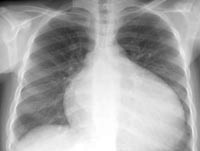

I42 Кардиомиопатия